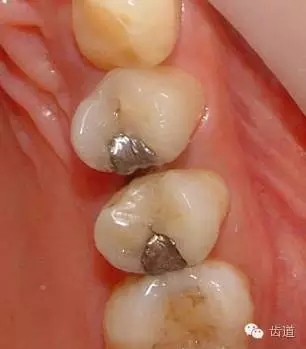

1、上頜前磨牙銀汞充填后食物嵌塞

2、去除銀汞充填物并作嵌體牙體預(yù)備

3、樹(shù)脂暫時(shí)嵌體覆蓋窩洞

4、瓷嵌體制作

5、瓷嵌體粘結(jié)